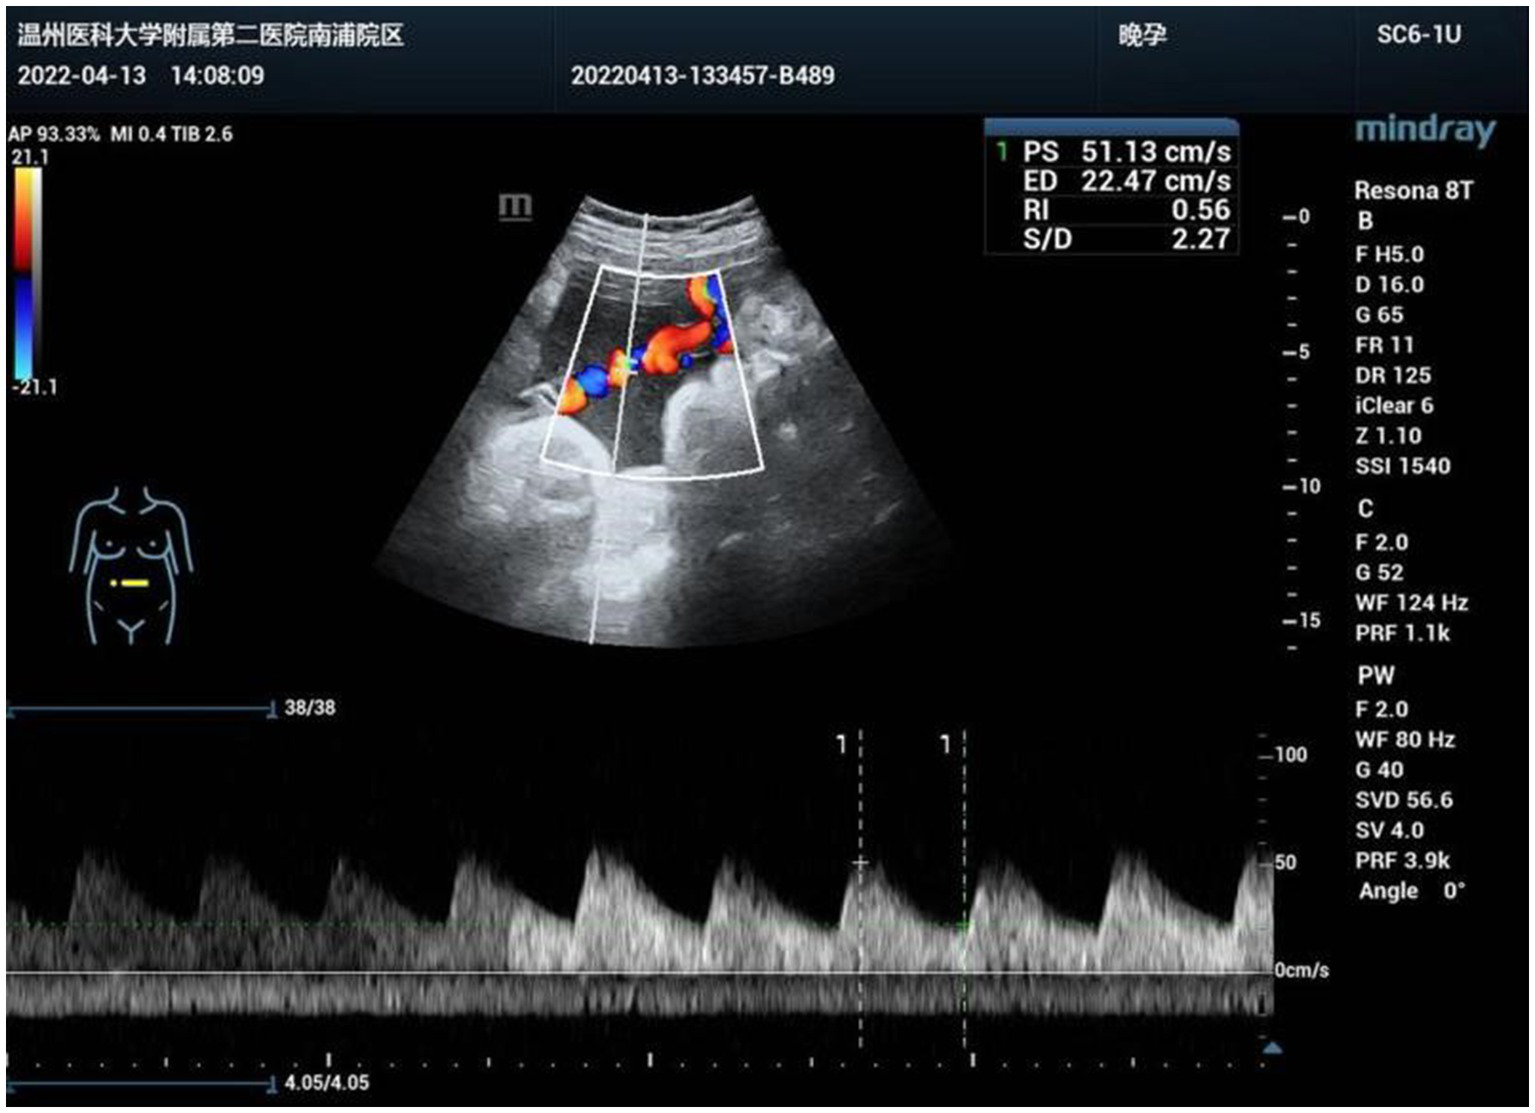

A 33-year-old primiparae was admitted in spontaneous labor to the labor and delivery service of the Second Affiliated Hospital of Wenzhou Medical University (Wenzhou, China) at 40 weeks of gestation. The patient was in good health during pregnancy, except for gestational diabetes mellitus. She had a routine obstetrical ultrasound at 21 weeks gestation, which revealed an abnormal bean-like dilation of the intra-abdominal umbilical vein, and umbilical vein thrombosis was suspected (Figure 1). Table 1 shows the umbilical vein flow pattern from 21 weeks to 40 weeks. Figure 2 shows the fetal color ultrasound image at 21 weeks. The fetal system ultrasound examination was performed at 21 weeks gestation and showed no abnormalities in the fetal biometric measurements, head, facial features, spine, chest, heart, diaphragm, stomach, abdominal wall, kidneys, bladder, forearm bones, lower leg bones, hands, feet, and bilateral adnexal regions of the pregnant woman. The placenta was located on the posterior wall of the uterus with normal thickness and grade, and the maximum depth of amniotic fluid pool was within normal range. The umbilical cord had a normal morphology with two umbilical arteries and one umbilical vein, and normal blood flow waveform in the umbilical artery. There was a local dilation of the intra-abdominal segment of the umbilical vein, but with normal blood flow parameters. Subsequently, she was scheduled for close follow-up with prenatal ultrasound every 2 weeks. Repeat ultrasound examination showed that the hyperechoic oval structure enlarged gradually, but there were no obvious abnormalities in umbilical cord blood flow, fetal growth or fetal heart monitoring. The delivery was uneventful, and an apparently healthy female infant weighing 2,830 grams was delivered. Apgar scores were 10 at 1 min and 10 at 5 min. The amniotic fluid was clear, and the placenta was delivered intact. No gross placental lesions or umbilical cord anomalies were identified. An abdominal ultrasound was performed soon after birth, which suggested thrombosis in the umbilical vein and portal vein. The baby was subsequently transferred to the neonatal intensive care unit (NICU) for clinical monitoring and observation.

| 38 weeks | 2022.04.13 | Intra-abdominal segment: locally dilated, cystic |

| Size: approximately 48 × 27mm | ||

| Blood flow signal: swirling | ||

| Fetal umbilical vein: localized tumor-like dilation |

The umbilical vein flow pattern from 21 weeks to 40 weeks.

Figure 2

Fetal color ultrasound image at 21 weeks.